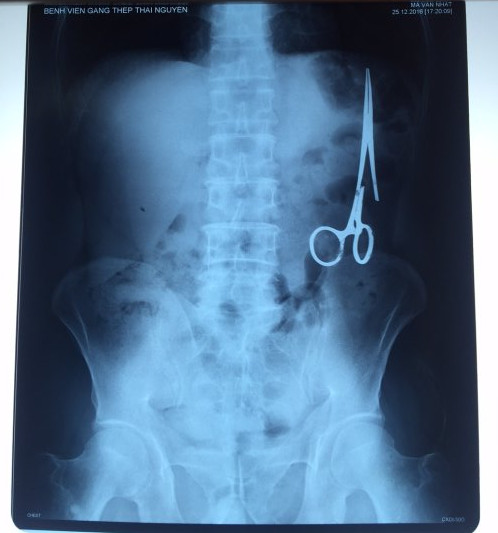

遺留在病人腹中的剪刀

據(jù)越南青年報(bào)1月2日?qǐng)?bào)道,在越南首都河內(nèi)醫(yī)療專家的幫助下,越南東北部的太原?。═hai Nguyen)鑄鋼醫(yī)院的醫(yī)生日前從54歲患者M(jìn).V.N腹中取出一把醫(yī)用剪刀。這把剪刀是此前曾為M.V.N手術(shù)的醫(yī)生遺留的,已經(jīng)在其腹中待了18年時(shí)間。

醫(yī)務(wù)人員表示,這把剪刀遺留在病人腹部左側(cè),與結(jié)腸緊挨著。剪刀的把手已經(jīng)生銹,部分器官也已經(jīng)與剪刀粘連起來。但在過去多年中,M.V.N沒有任何不適感覺,也從未因?yàn)榱粼诟怪械募舻兑l(fā)的相關(guān)問題去看過醫(yī)生。直到2016年12月,M.V.N因?yàn)樵庥隽艘粓?chǎng)車禍,才到鑄鋼醫(yī)院進(jìn)行身體檢查。

超聲波檢查顯示,M.V.N的腸子中有個(gè)奇怪物體,看起來就像醫(yī)用剪刀。M.V.N證實(shí),他曾于1998年6月份在北江省綜合醫(yī)院接受手術(shù),在此后也從未進(jìn)行過任何手術(shù)。近來,他感到腹部有些疼痛,并試圖通過服用藥物治療。12月27日,M.V.N回到北江省綜合醫(yī)院再次進(jìn)行超聲波檢查,顯示其腹部的確存在怪異物體。